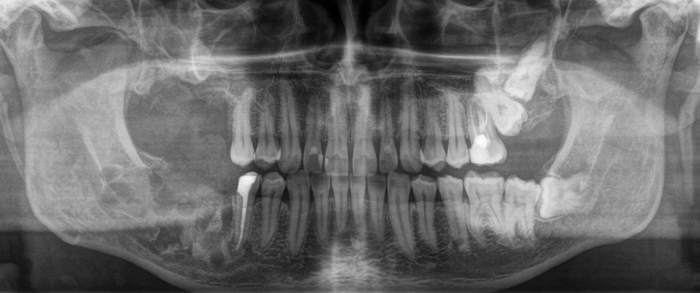

На прием пришла девушка с пожеланием восстановить удаленный ранее в другой клинике зуб на верхней челюсти справа. Ну что ж, без проблем. Направляю пациентку на компьютерную томографию для оценки ситуации. И вдруг я вижу «её» – притаившуюся в пазухе омерзительную восьмерку, которая, противно ухмыляясь, смотрит прямо на меня.

Кроме того, что она сама по себе противная, так еще она успела навредить 7му зубу.

Красным пунктиром отмечено разрастание фолликулярной кисты, которая распространилась в область корней зуба по соседству.

Зуб, как мы выяснили, не самый приятный. Удалять его не особо-то и хотелось, поэтому я принял решение за ним понаблюдать и повторить снимок через год.

Вжух и год позади:

В целом, каких-то явных изменений нет. В подтверждение тому, что это не один и тот же снимок, вы можете обратить внимание, что на имплантате уже установлена постоянная коронка.

Добрый вечер… А что это значит?... Прекрасно видно, что фолликулярная киста начала расти и оттеснять зуб мудрости дальше в пазуху, что несколько затрудняет его удаление. Блять, подумал я, надо было сразу удалять.